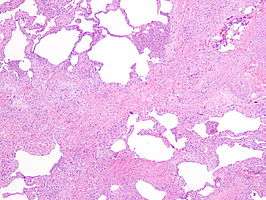

UIP may be diagnosed by a radiologist using computed tomography (CT) scan of the chest, or by a pathologist using tissue obtained by a lung biopsy. Radiologically, the main feature required for a confident diagnosis of UIP is honeycomb change in the periphery and the lower portions (bases) of the lungs.[2] The histologic hallmarks of UIP, as seen in lung tissue under a microscope by a pathologist, are interstitial fibrosis in a "patchwork pattern", honeycomb change and fibroblast foci (see images below).[3]